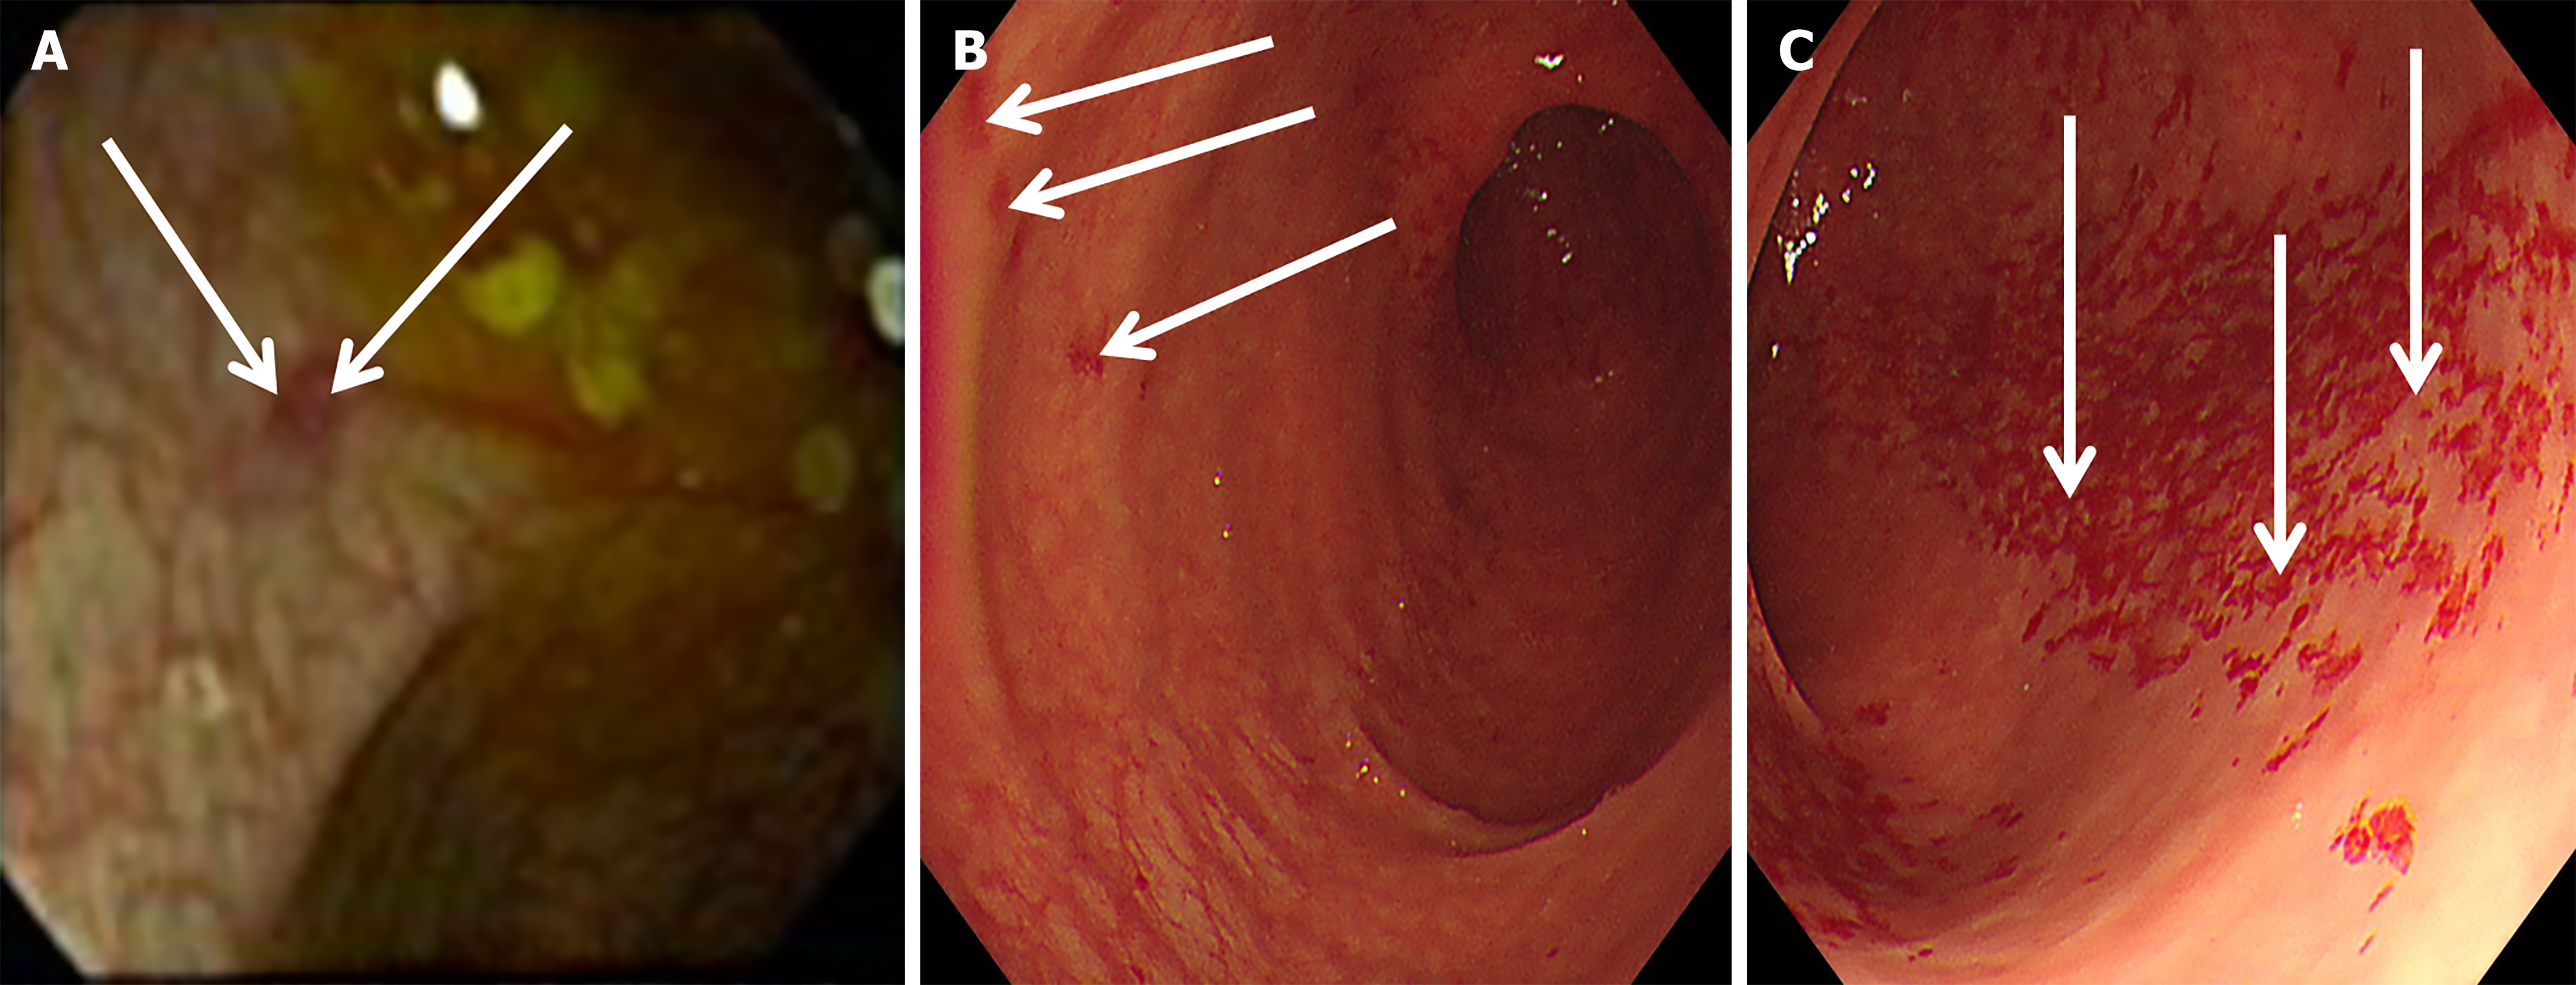

Figure 1 Electronic colonoscopy images on two occasions.

A: On day 8 of diarrhea, electronic colonoscopy (arrows) revealed a patchy erosion measuring approximately 4 mm × 3 mm in the transverse colon (hepatic flexure) (obtained by an experienced endoscopist). Image resolution is limited solely due to suboptimal bowel preparation; however, the colonic erosion remains discernible. The location of the erosion corresponded to the presentation of right upper quadrant pain; B and C: On day 64 of diarrhea, multiple erosions were observed in the ascending colon (arrows in B) and the transverse colon (arrows in C). Compared to panel A, the area of colonic mucosal erosion shown in panels B and C had significantly enlarged, which was consistent with the worsening diarrhea symptoms.